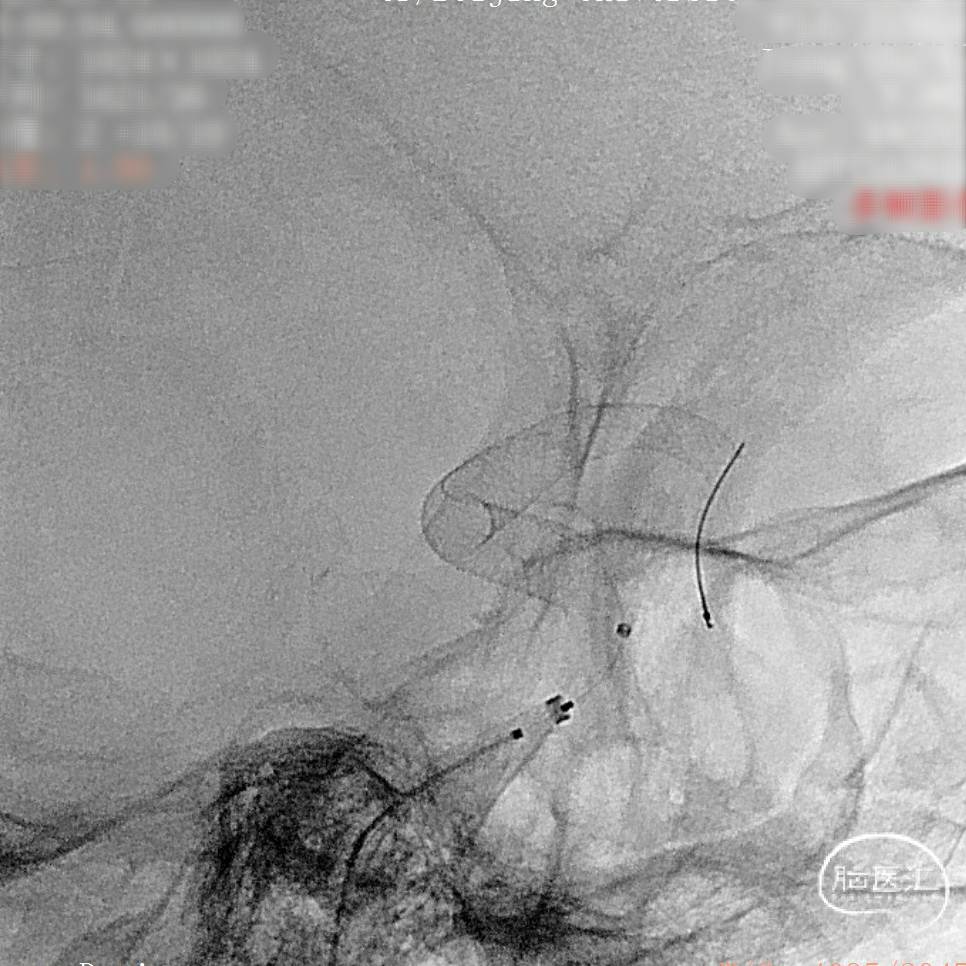

支架完全释放。

造影明确打开贴壁满意。

正侧位造影:支架放置后可见动脉瘤内造影剂明显滞留。